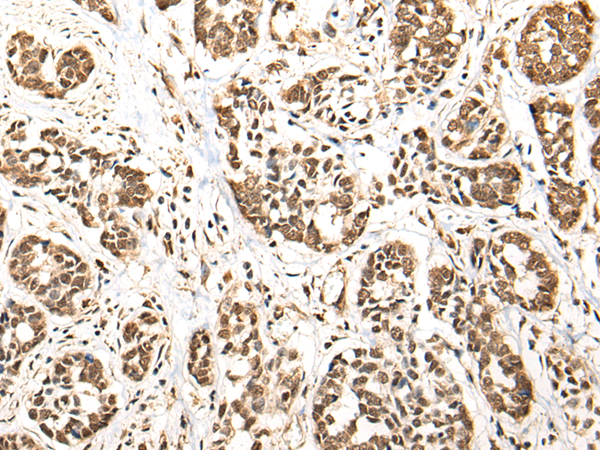

ELISA, IHC |

IHC positive control: |

Human liver cancer and human esophagus cancer |

IHC Recommend dilution: |

25-100 |